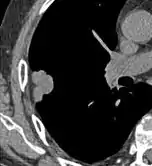

Lobulated nodule.[9]